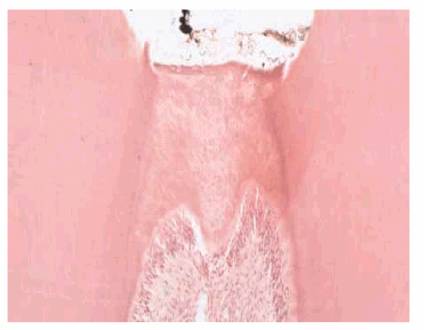

Secondary Dentin

Histologically and physiologically, there is a difference between reparative

and secondary dentin. Secondary dentin begins forming soon after the tooth

erupts into occlusion and continues to form throughout the pulp's life. This

tooth structure is deposited over the primary dentin (Figure 19-31) throughout the entire chamber and

canal in response to stimuli within the limits of normal biologic function:

mastication, light thermal changes, chemical irritants, and slight trauma. The

newly deposited dentinal tubules are smaller, exhibit more curves, and form a

protective barrier for the pulp as the size of the pulp cavity is reduced.

Reparative dentin forms as a direct response to injury. Although the deposition

is not uniform in thickness, this dystrophic calcification may completely

occlude the canal, reduce the blood supply, necrose the tissue, and complicate

the eventual endodontic therapy.

Figure 19-31: Secondary dentin represents the continuing slower circumpulpal deposition of dentin after root formation is complete.